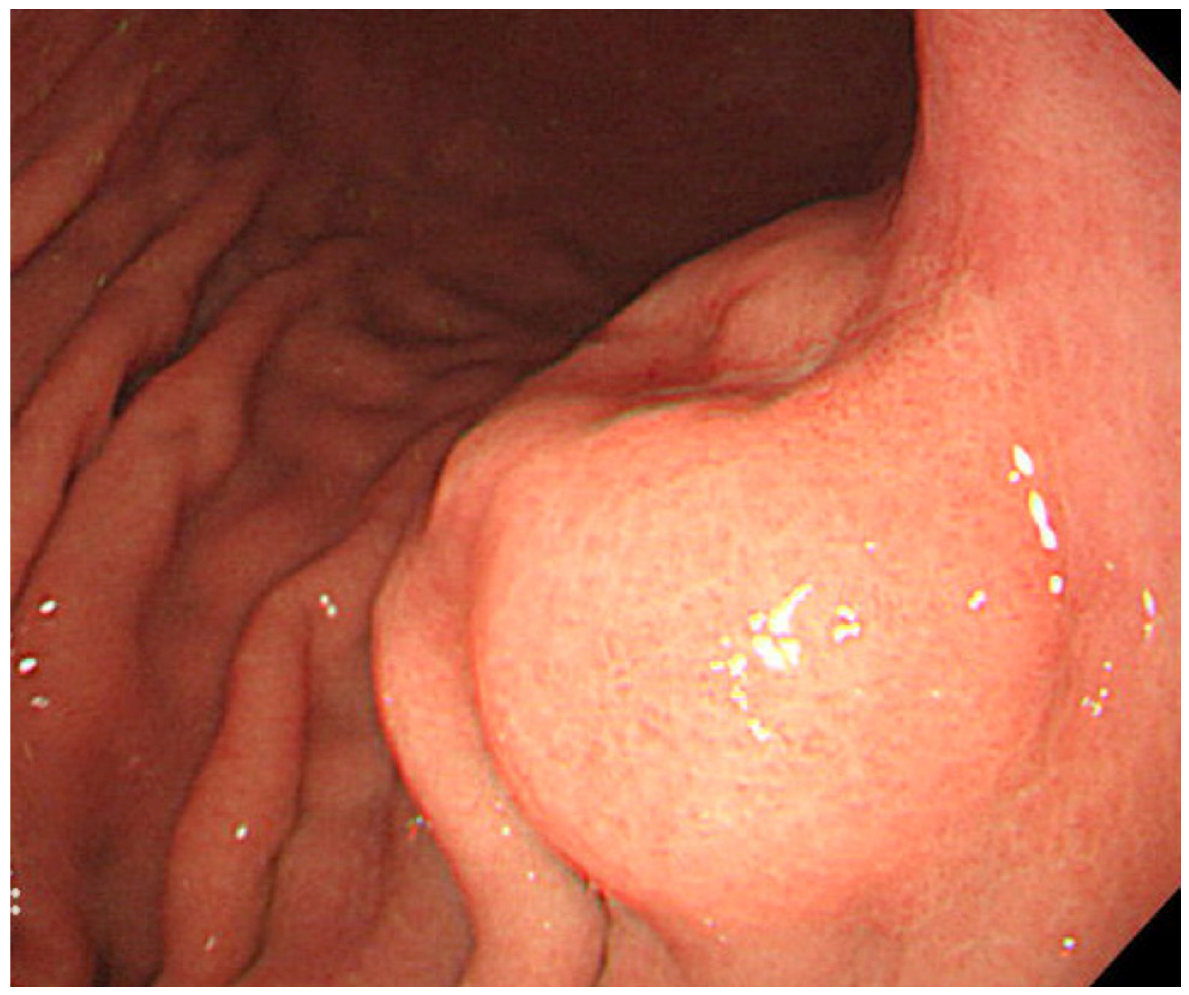

- Yanai, H.; Nishikawa, J.; Mizugaki, Y.; Shimizu, N.; Takada, K.; Matsusaki, K.; Toda, T.; Matsumoto, Y.; Tada, M.; Okita, K. Endoscopic and pathologic features of Epstein–Barr virus–associated gastric carcinoma. Gastrointest. Endosc. 1997, 45, 236–242. [Google Scholar] [CrossRef]

- Nishikawa, J.; Yanai, H.; Mizugaki, Y.; Takada, K.; Tada, M.; Okita, K. Hypoechoic submucosal nodules: a sign of Epstein–Barr virus–associated early gastric cancer. J. Gastroenterol. Hepatol. 1998, 13, 585–590. [Google Scholar] [CrossRef]